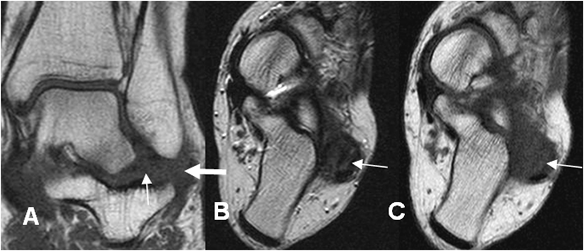

Fig 65 B. Lesión ligamentaria crónica.

A: RM coronal en T1. Pérdida de la señal normal de los ligamentos peroneoastragalino posterior (Flecha delgada) y peroneocalcaneo (Flecha gruesa).

B: RM axial en T2 y C: RM axial en T1. Los componentes del ligamento colateral lateral están engrosados y con alteración de su señal, por lesión crónica.